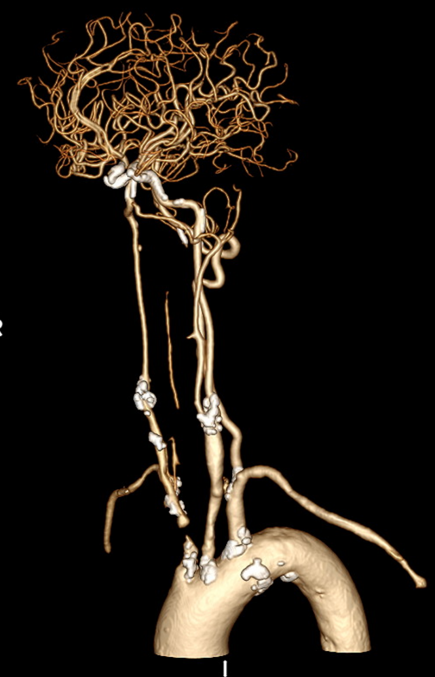

CASE 2:69岁男性,左侧颈动脉支架术后再狭窄,IVL治疗后管腔获得良好,支架置入后残余狭窄低。

左侧颈动脉支架

术后再狭窄

IVL后管腔

获得良好

支架后

残余狭窄低